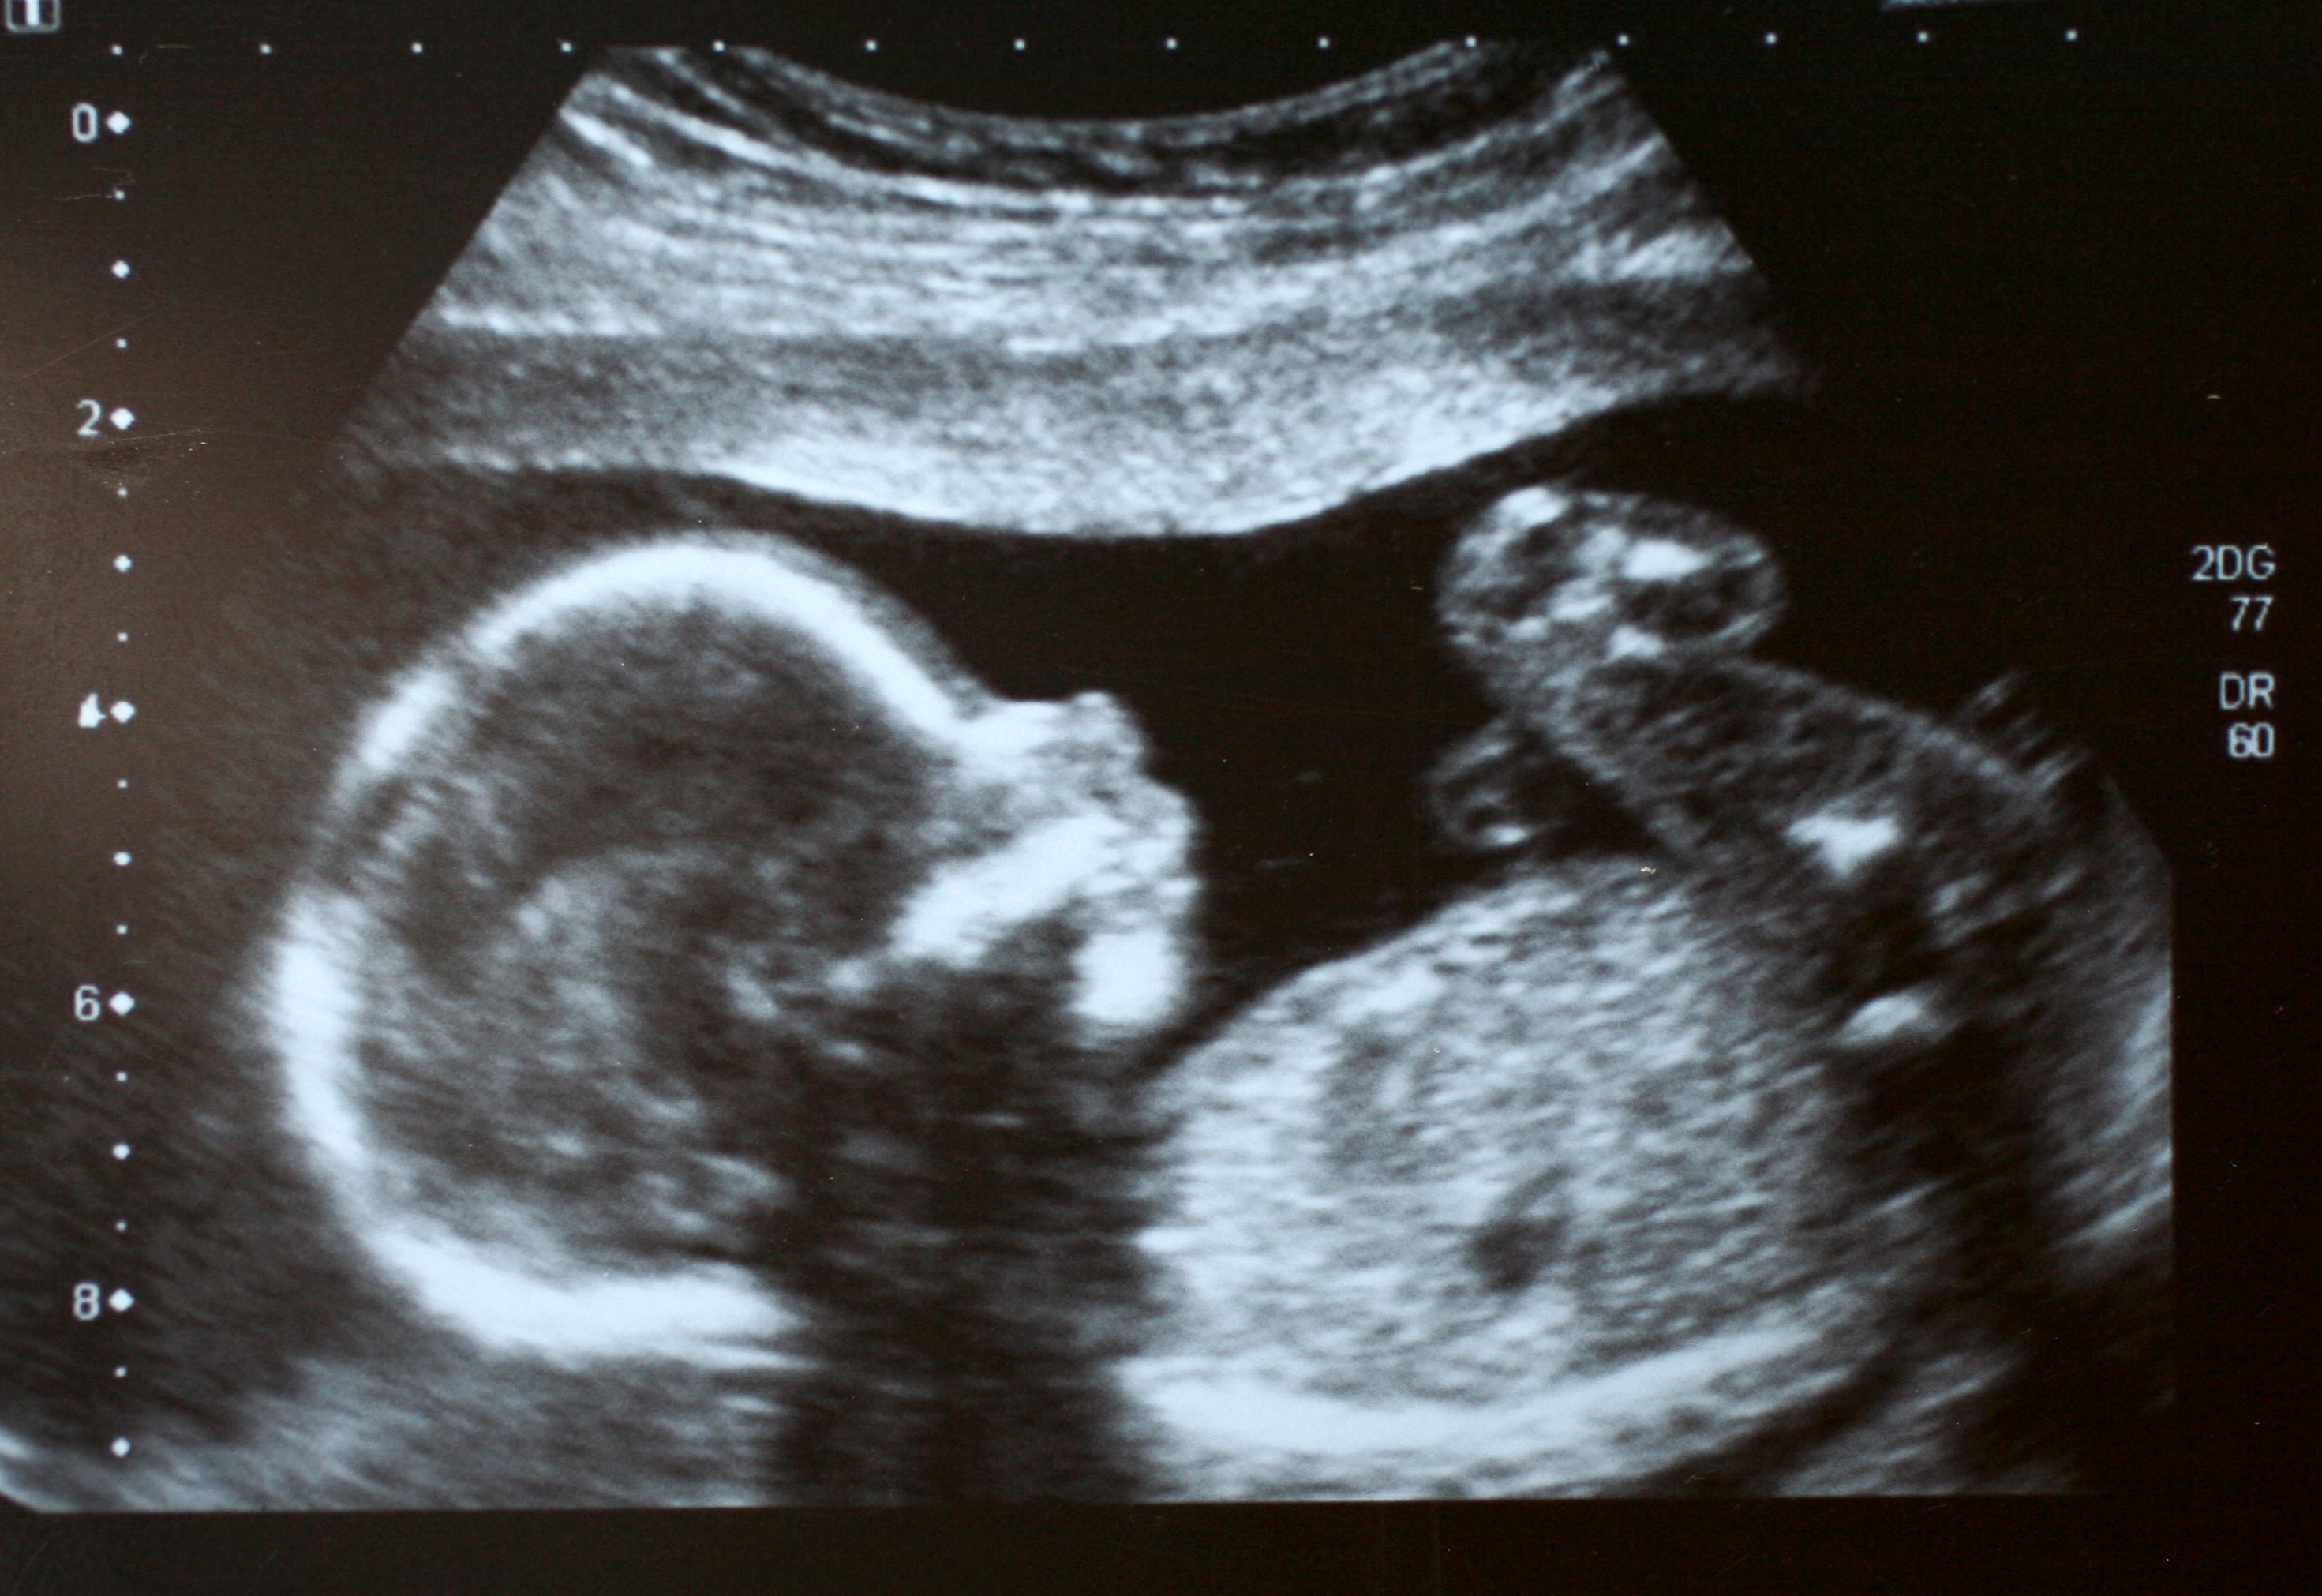

Following the first-ever treatment for spinal muscular atrophy in the womb, physicians say a 2-year-old girl shows no signs of the rare genetic disorder.

Because the protein is most needed in the third trimester of fetal development and the first three months of life after birth, St. Jude’s says that symptom severity is closely linked with intervention time. So, they launched the clinical protocol to study risdiplam in a single patient. The Food and Drug Administration approved the study.

The parents of the patients had a prior infant born with Type 1 and were known carriers of genetic variants. Testing confirmed that their child would likely be born with Type 1. The idea of giving the drug in utero came from the parents, and doctors gave the mother the drug within the final six weeks of her pregnancy.